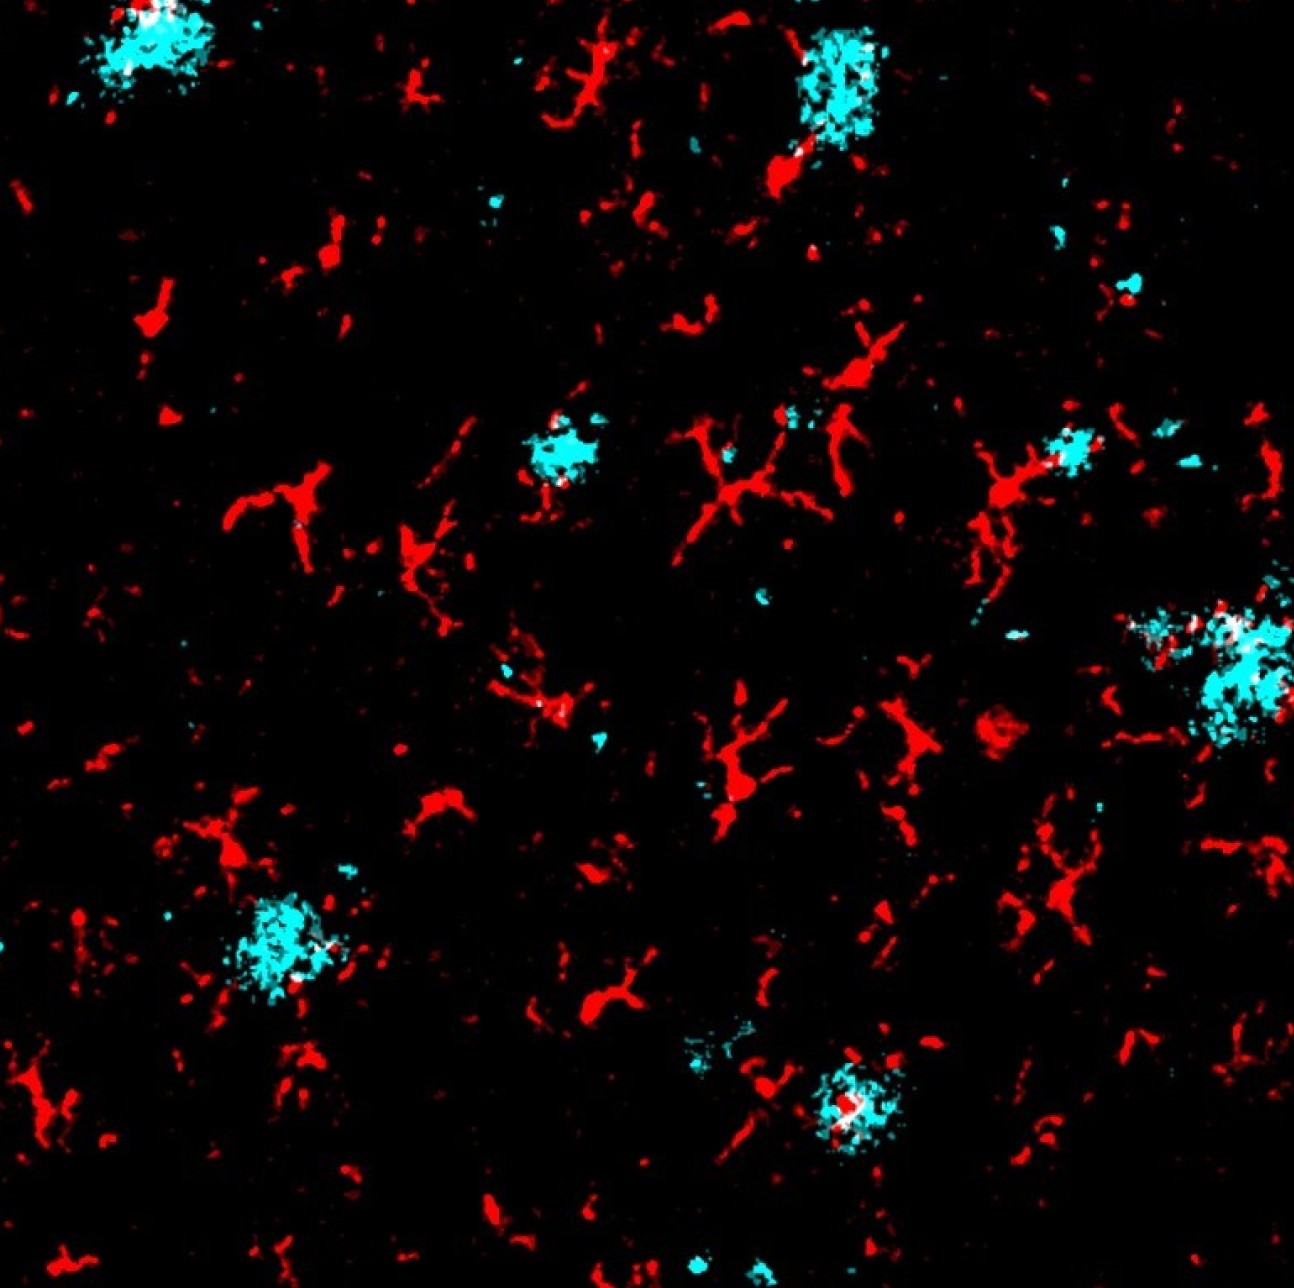

Microglia and Amyloid Plaques - Callum Muirhead and the Multi-Omics Atlas Project team

"Imaging mass cytometry image of amyloid plaques (red) and microglia (cyan)."

"Co-localization of amyloid plaques and microglia (white)."